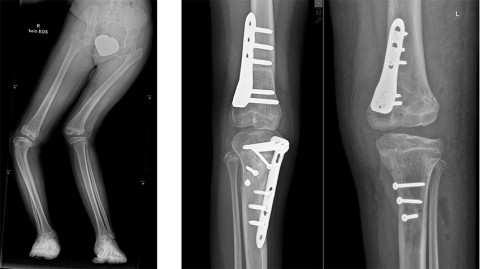

Aufgrund des Befundes hatten die Ärzte an der Schulthess Klinik den Verdacht auf eine schwerwiegende Bindegewebserkrankung mit der Folge beidseitig, vollständig luxierter Kniescheiben und durch die Instabilität bedingter schwerer, knöcherner Deformitäten. Im Endeffekt bestanden vor den Operationen funktionsuntüchtige Kniegelenke mit fehlverlaufenden Muskelzügen, knöchernen Fehlstellungen und Torsionsproblemen.

Rechts: Röntgenbild nach der Operation.

Im März 2022 fand die erste von insgesamt vier Operationen statt, bei der eine aufwändige Neupositionierung der Kniescheibe und insgesamt drei Umstellungsosteotomien am rechten Bein vom kinderorthopädischen Team um Dr. Hannes Manner durchgeführt wurden. Da sich die Operation auf der rechten Seite als komplexer als erwartet herausstellte und 4.5 Stunden dauerte, konnte anfänglich nur das eine Bein korrigiert werden. Einige Monate später wurde Mara erneut in der Schulthess Klinik aufgenommen und die Operation auf der linken Seite wurde ebenfalls erfolgreich durchgeführt. Sie war jeweils nur eine Woche bei uns, damit sie sich nicht zu sehr von ihrer «neuen Heimat», dem Friedensdorf in Dinslaken entfremdet. Das Mädchen hat die gesamte Situation bravourös gemeistert.